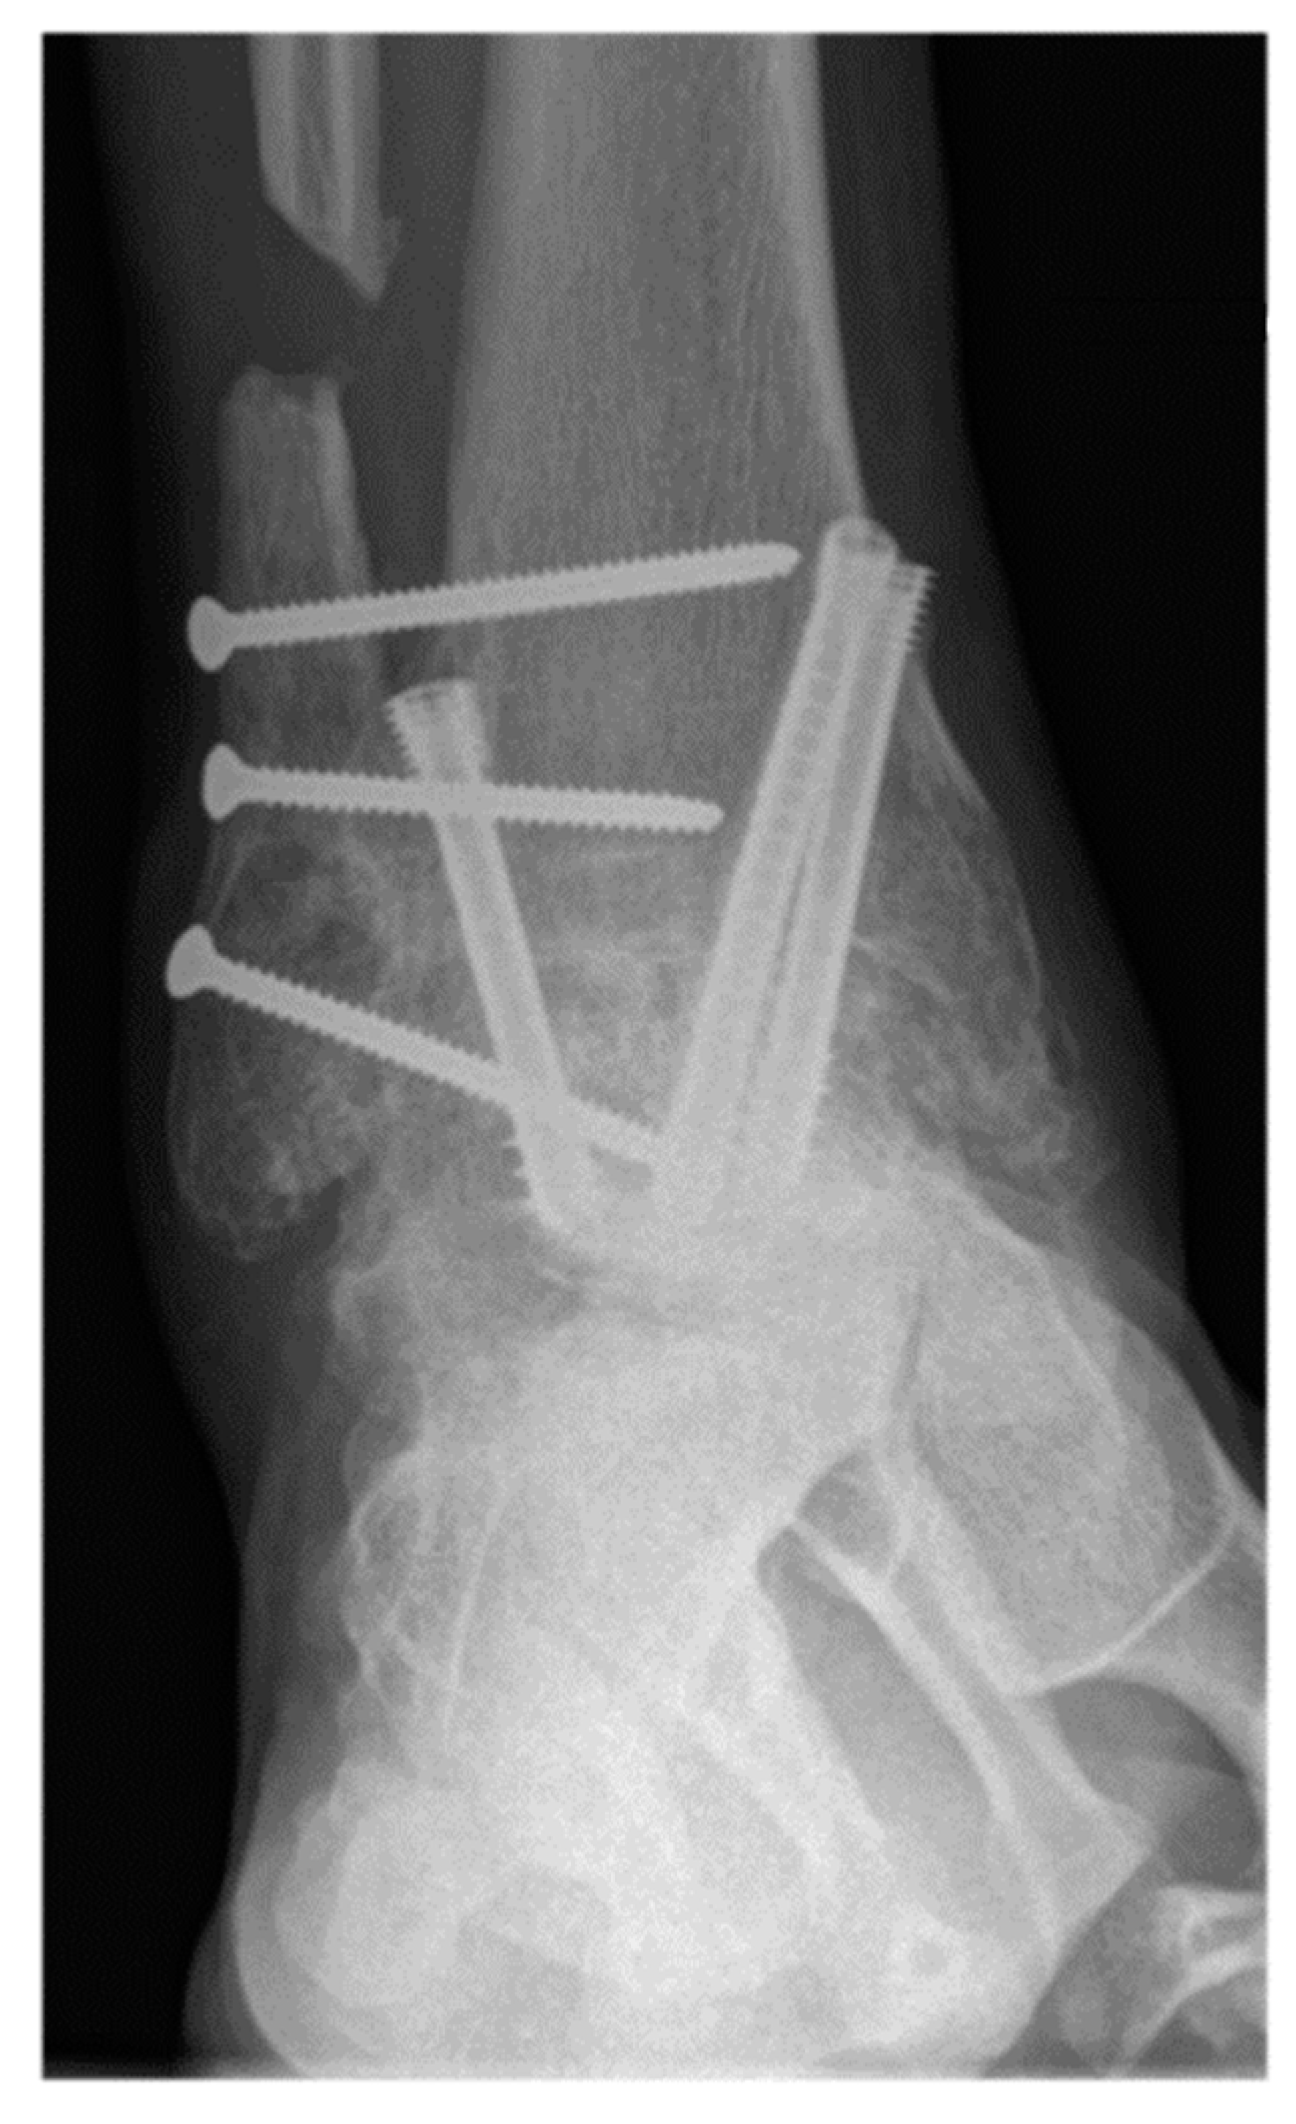

Figure 3.

A 57-year-old male patient presenting complete union of the tibiotar and distal tibiofibular joints at 6 months follow-up.

The primary outcome measure was nonunion rate of tibiotalar arthrodesis [2]. Union was defined based on patient reported symptoms and clinical physical examination criteria (no pain, no warmth, improvement in swelling, and stability to stress) and radiographic criteria (visible trabecular bridging across the arthrodesis site and no lucency around the hardware) [40]. Appropriate osseous union was defined as trabecular bridging across the tibiotalar joint (at least 80%) within 6 postoperative months [41] (Figure 3 and Figure 4). In patients with nonunion, computerized tomography (CT) was utilized for further assessment and was evaluated by independent radiologist not involved in any of surgeries. Secondary outcome measures were wound complications, return to the operating room, and rate of development of post-operative deep vein thrombosis (DVT), or pulmonary embolism (PE).